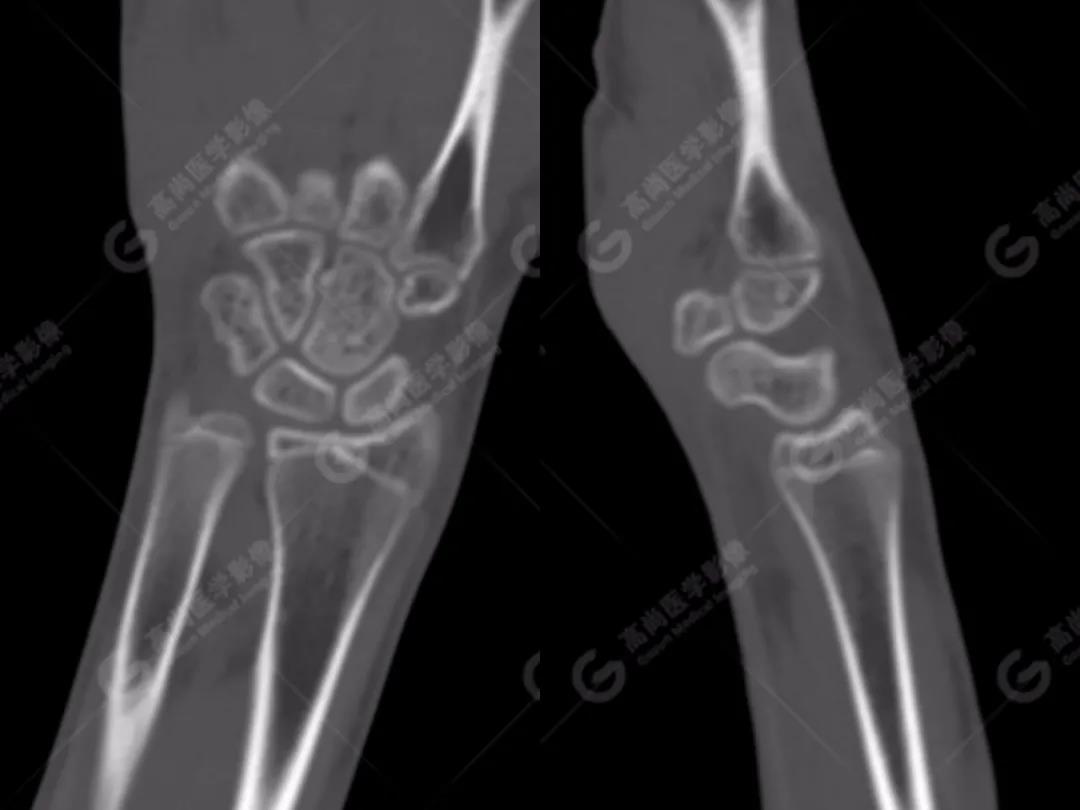

2、常規(guī)CT圖像

常規(guī)CT平掃灰階圖像上雙腕關節(jié)仍然未見明顯骨折征象。